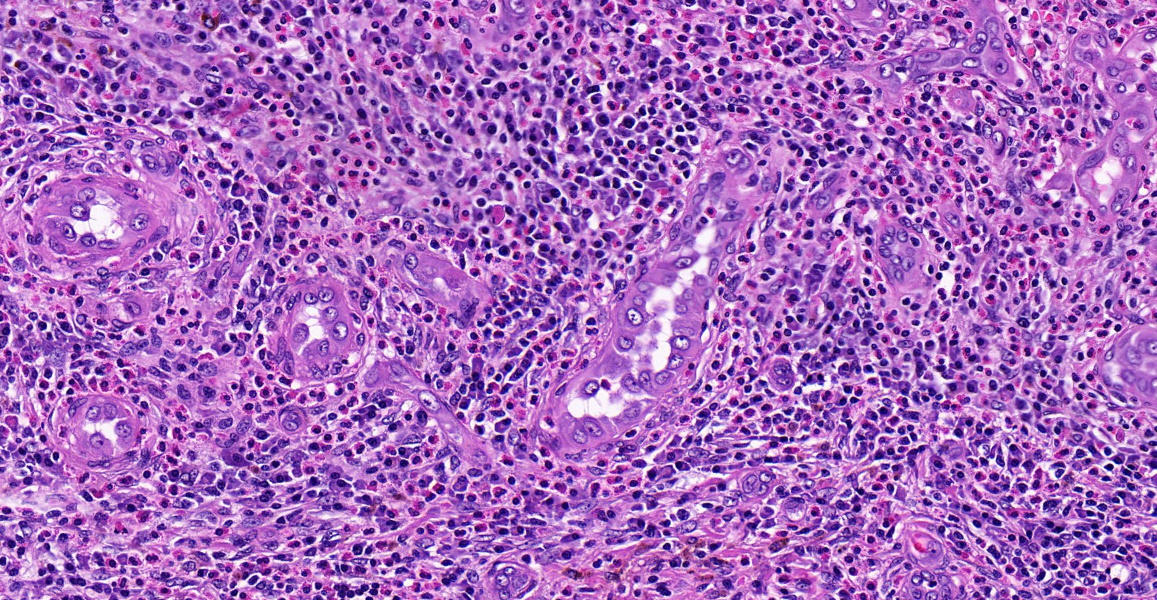

🦴Dedifferentiated chondrosarcoma.🦴 Left: high grade noncartilaginous sarcoma / Right: conventional chondrosarcoma. #Pathology #AnatomiaPatologica #Pathologyst #BSTpath #PathTwitter

🦴Dedifferentiated chondrosarcoma.🦴

Left: high grade noncartilaginous sarcoma / Right: conventional chondrosarcoma.